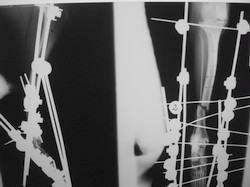

PRÁCTICAS CURSO DE FIJACIÓN EXTERNA PERFECCIONAMIENTO.

Artrodesis tarso.